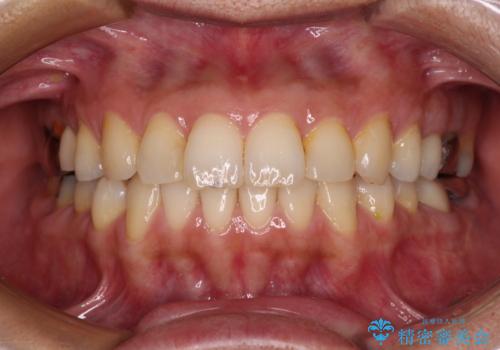

口元の突出感とデコボコがあり、上下左右の小臼歯4本を抜歯して矯正治療を行う方針としました。(右上は欠損のため計3本抜歯)

イレギュラーな大臼歯抜歯矯正であったため、治療期間の長期化が想定されましたが、何とか3年ちょうどで終えることができました。

今後は目立っている銀歯を中心にセラミッククラウンなどへ交換していく予定です。